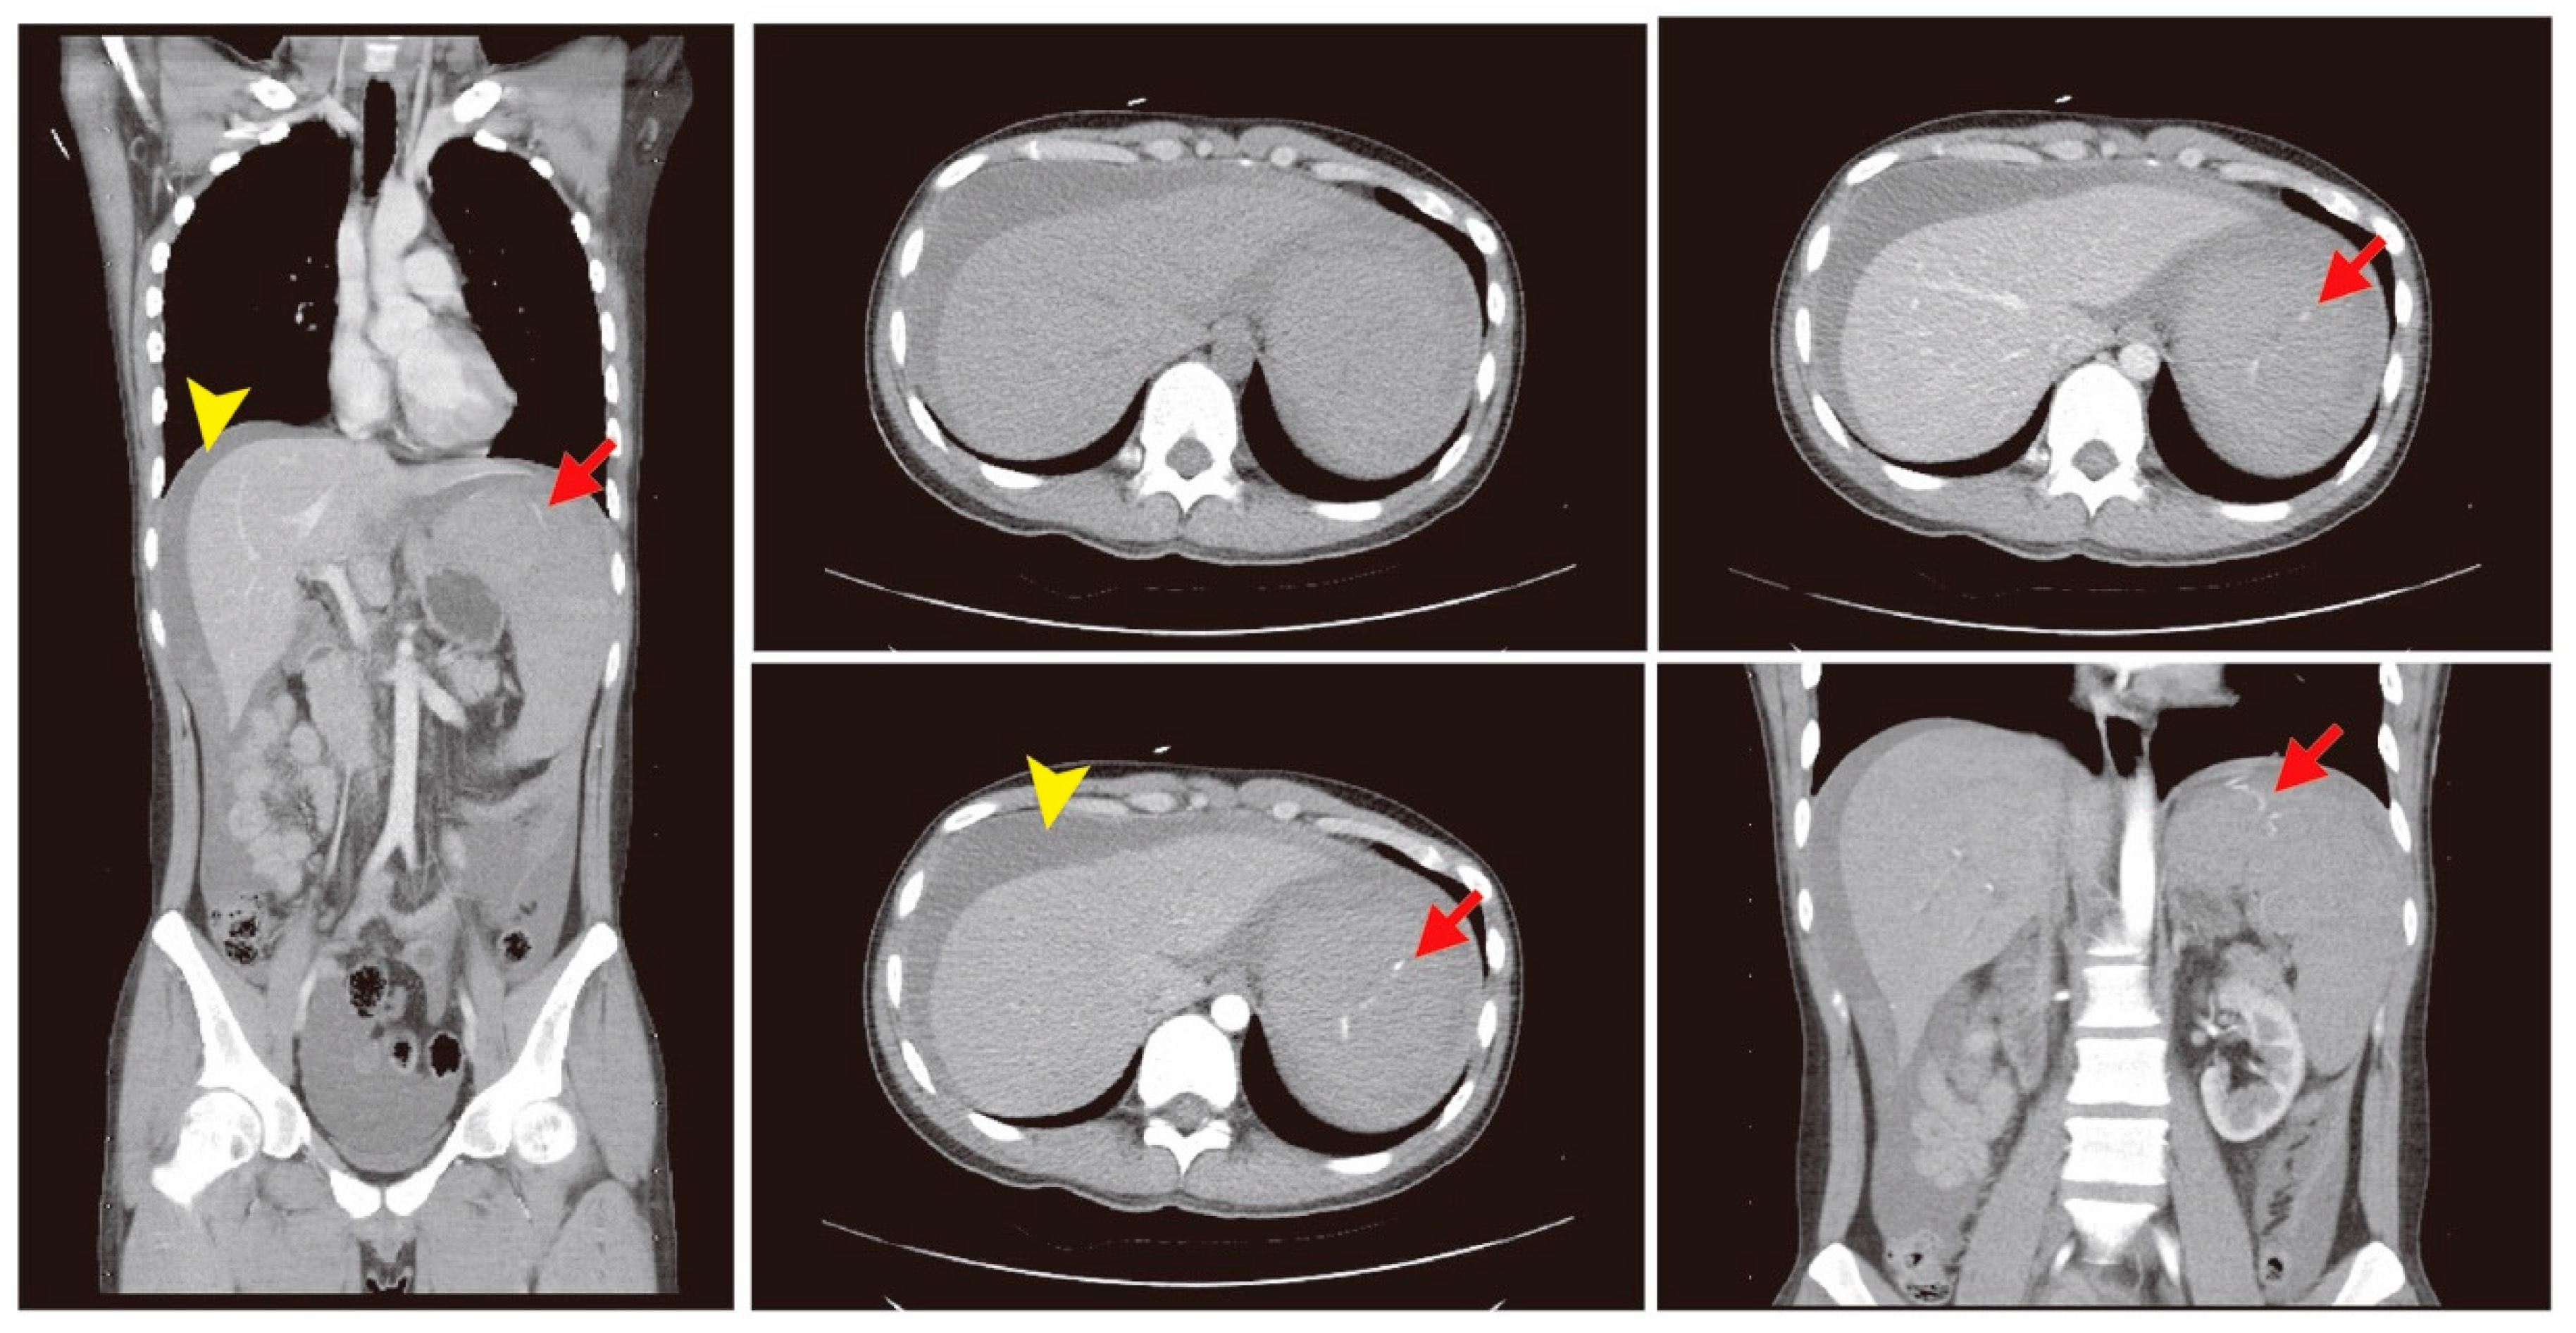

The patient was hospitalized in the intensive care unit (ICU) for post-embolization care. There was no progressive abdominal pain. The follow-up abdominal circumference was decreased, which reflected that intra-abdominal bleeding was under control due to a decreased amount of ascites (Figure 3). The follow-up CT scan revealed the spleen hemorrhage had been controlled through coil embolization (Figure 4). The hemoperitoneum also improved. A bone marrow examination showed sheets of small blasts with scant cytoplasm. Monotonous blasts comprised more than 95% of nucleated cells. ALL with scant cytoplasm was diagnosed with BCR-ABL (+), Periodic acid-Schiff (PAS) (−), peroxidase (−), TdT (< 1%), CD34 (< 1%), CD117 (< 1%), MPO (+, 60%), and CD20 (+, 5–10%). Broad-spectrum antibiotics, including Meropenem, Mycamine, and Teicoplanin, were administered to treat a severe immunocompromised infection due to persistent fever. After supportive care, extubation was performed and the patient stabilized. Target therapy with the agent Dasatinib (50 mg three times per day) combined with chemotherapy agents, including Vincristine and Methotrexate, controlled the progression of ALL. Intrathecal chemotherapy with Methotrexate (15 mg) and methylprednisolone (40 mg) was administered. Bone marrow aspiration and cytology were performed again and revealed normal cellularity. There were no significant side effects or complications. He was regularly followed-up at the outpatient clinic. The follow-up laboratory data is shown in Table 2. A patient consent form has been obtained from the patient.

Figure 4.

In the follow-up computed tomography (CT) scan, partial infarct of the spleen (red arrows) with two-coil embolization was noted, with improved hemoperitoneum (yellow arrow heads).